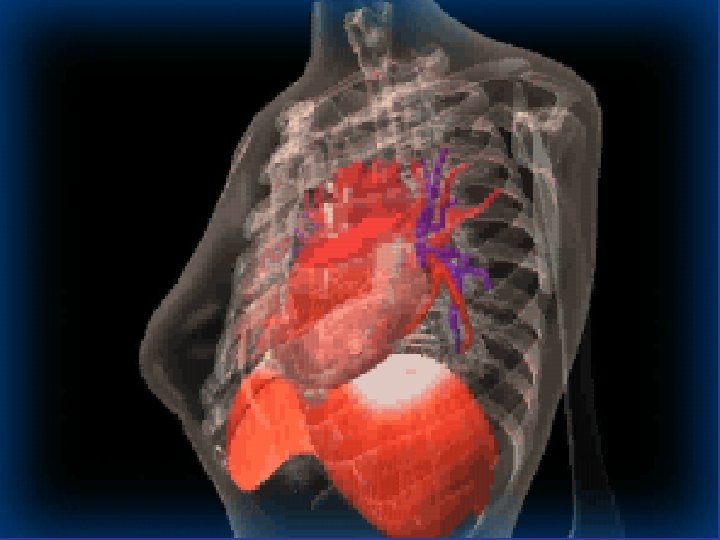

* trachea ; position & caliber * hila : lymphadenopathy * mediastinum contour

* trachea ; position & caliber * hila : lymphadenopathy * mediastinum contour : ? mass * heart : cardiac configuration Mediastinum, heart and hila